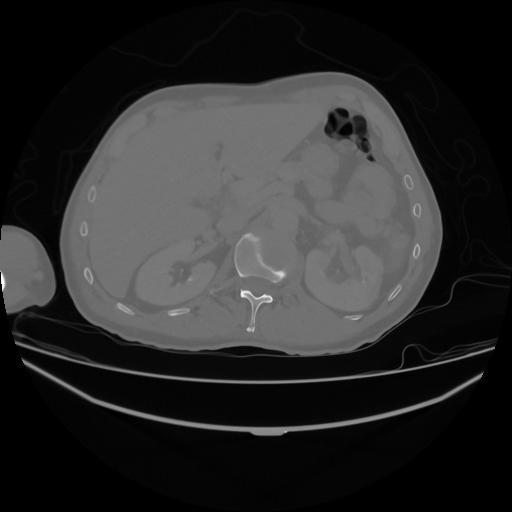

5 CUERPO,CE,Vol,1.0,CUERPO,,